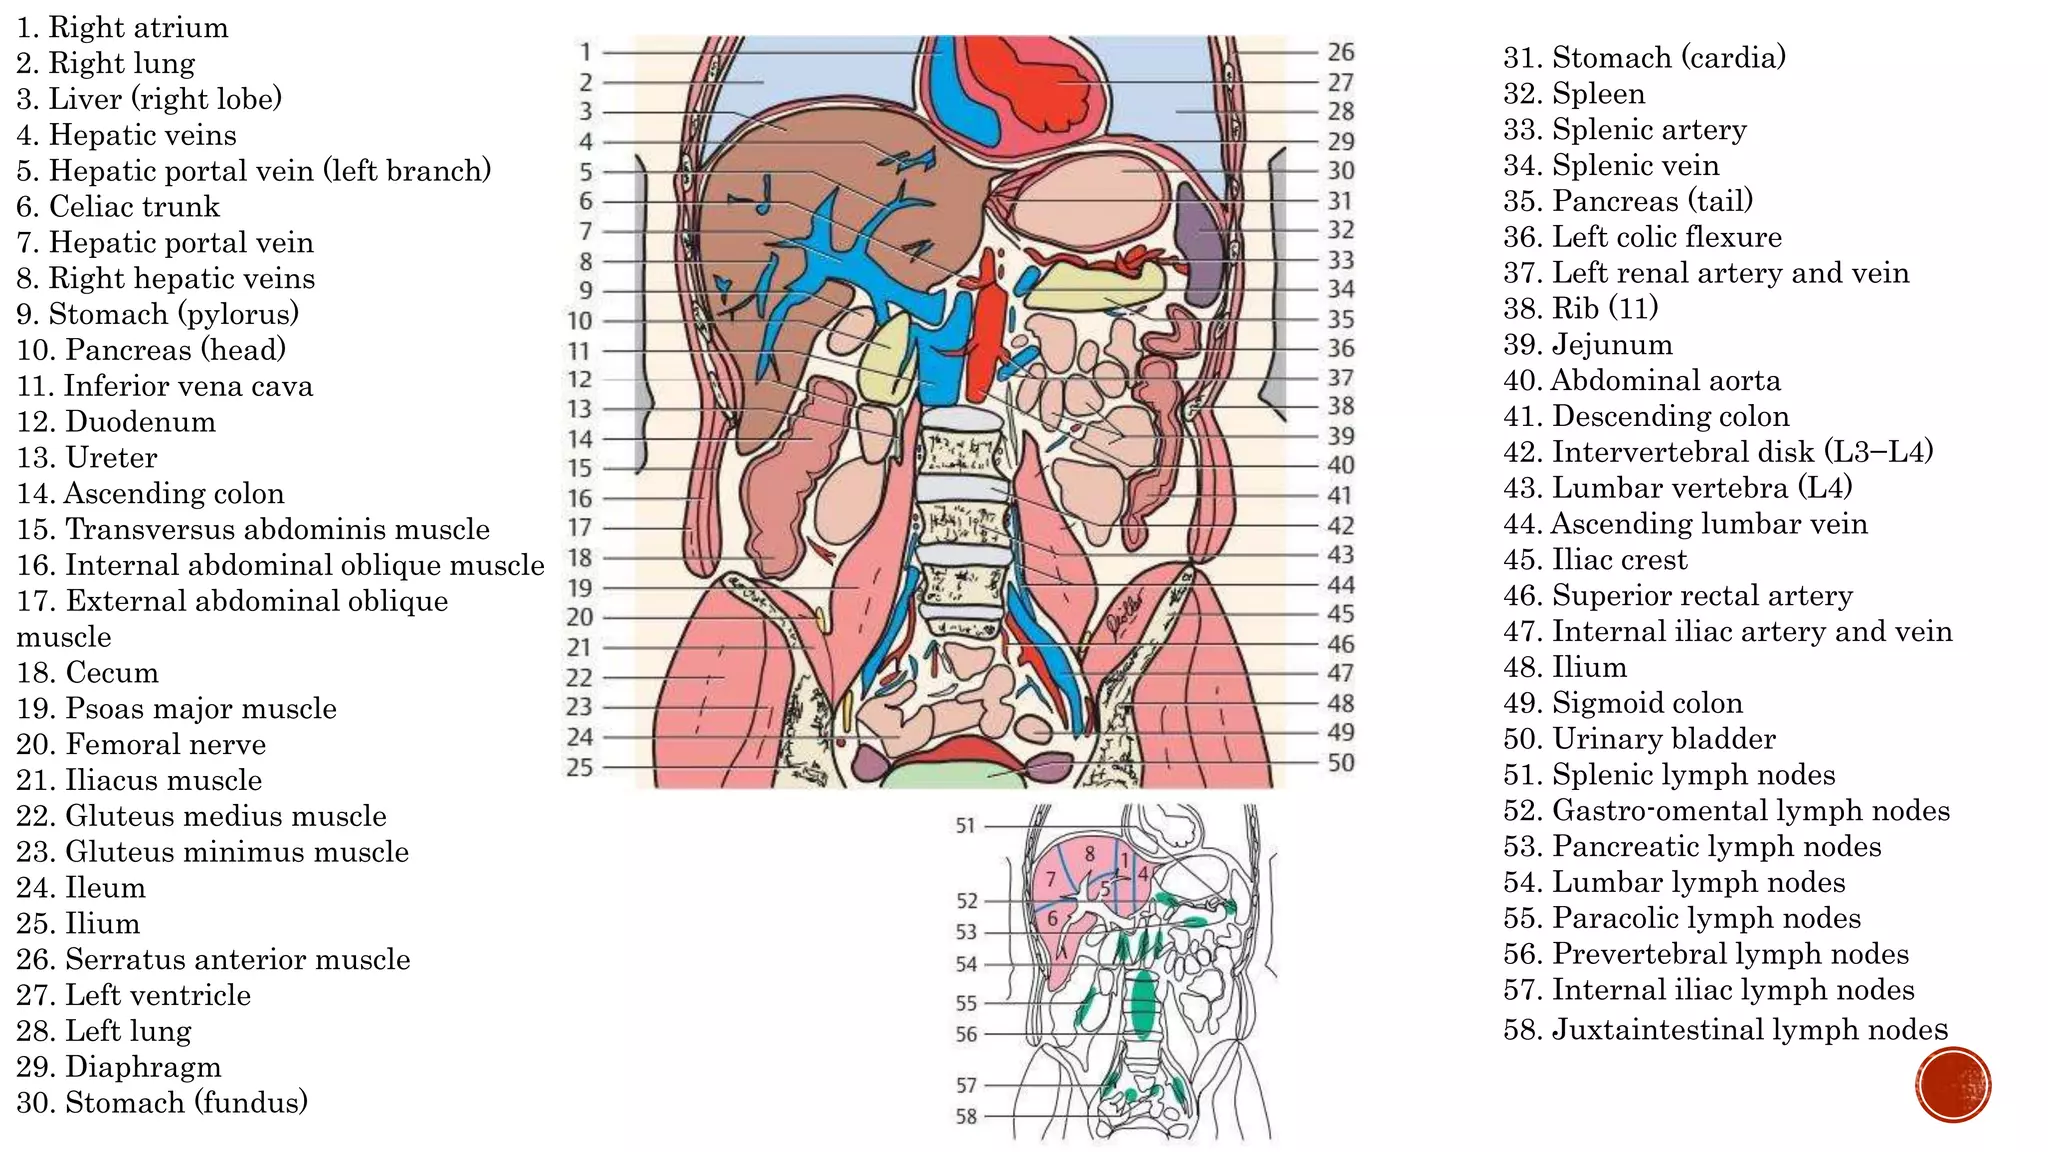

The document describes the anatomy of the abdomen and pelvis region of the human body. It lists over 40 structures and their locations, including major organs like the liver, kidneys, intestines, blood vessels and muscles of the abdominal wall and pelvis. The structures are grouped into sections focusing on different anatomical areas like the abdomen, retroperitoneum, pelvis and gluteal region.